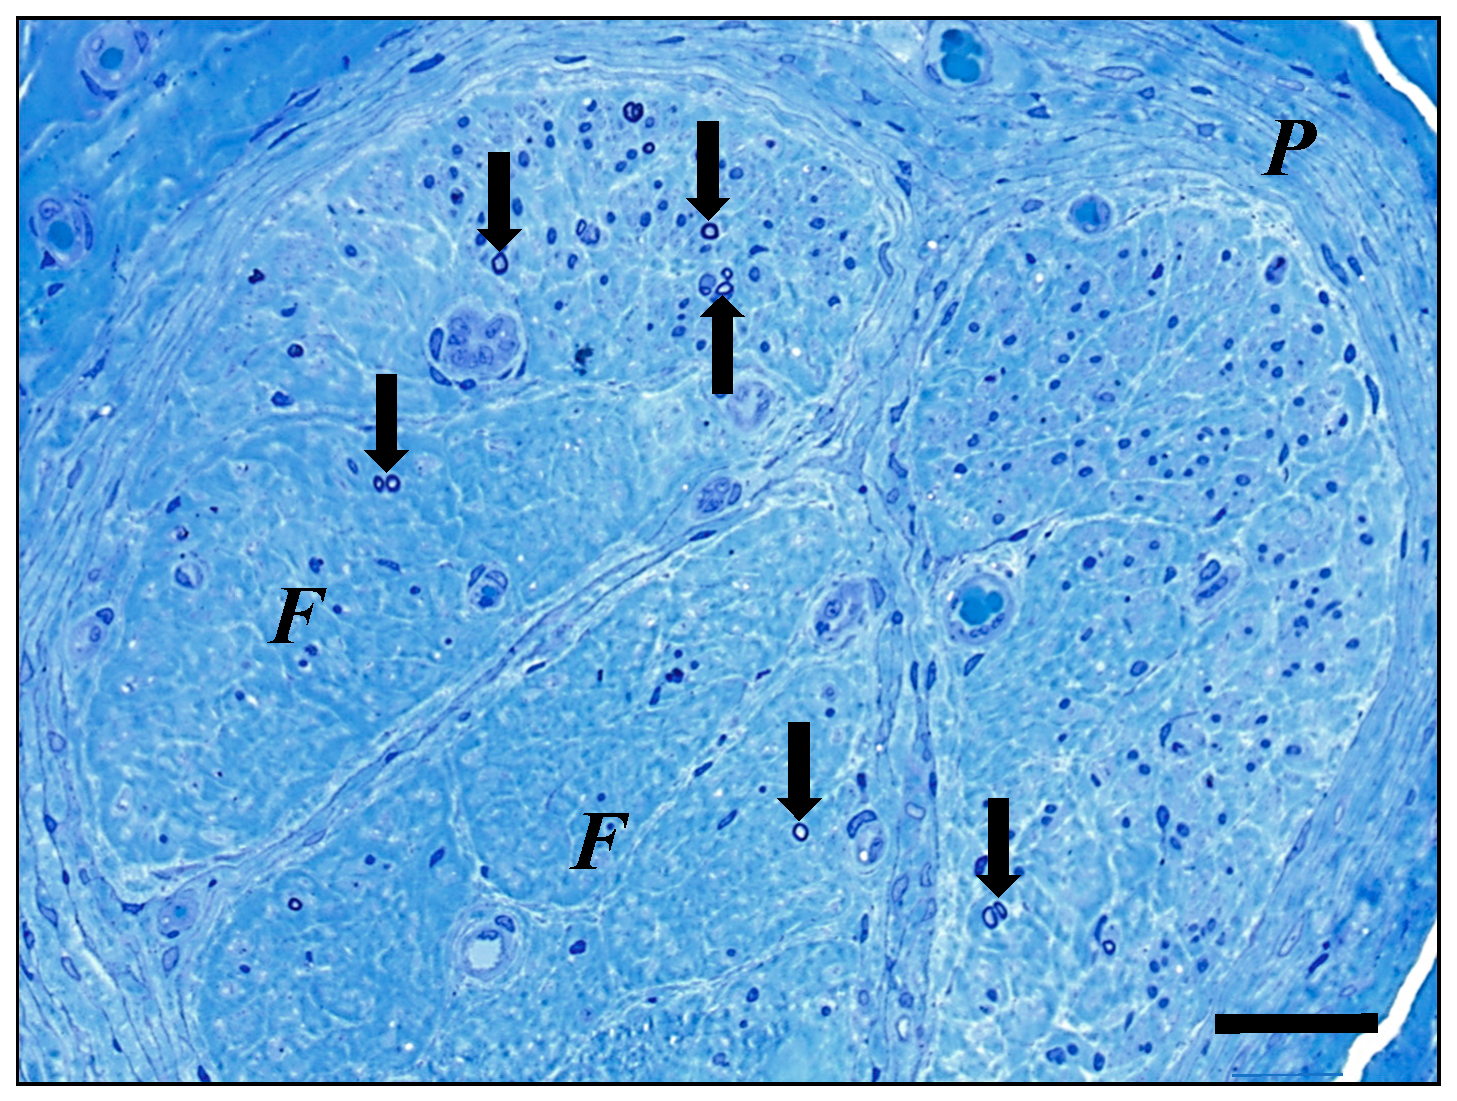

- Weis, J.; Katona, I.; Nikolin, S.; Nobbio, L.; Prada, V.; Grandis, M.; Schenone, A.J. Techniques for the standard histological and ultrastructural assessment of nerve biopsies. J. Peripher. Nerv. Syst. 2021, 26 (Suppl. S2), S3–S10. [Google Scholar] [CrossRef] [PubMed]